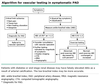

What happens to the ankle-brachial index (ABI) in patients with claudication as they go from resting to walking?

The ABI drops (ABI may be 0.9 but can drop to less than 0.6 with exercise, resulting in pain)

[UpToDate: Some patients with PAD who have a classic history of claudication, and others with atypical extremity pain, have a normal resting ABI (0.91 to 1.30). For these patients, exercise testing is indicated. Abnormal exercise ABIs support a diagnosis of PAD as the etiology of their symptoms.

The study should be performed in a vascular laboratory using a standardized exercise protocol (fixed or graded) and a motorized treadmill to ensure reproducibility of measurements of pain-free walking distance and maximal walking distance.

Exercise treadmill tests are useful for providing the most objective evidence of the magnitude of the functional limitation in patients with claudication, and can also be used to guide the response to treatment.]